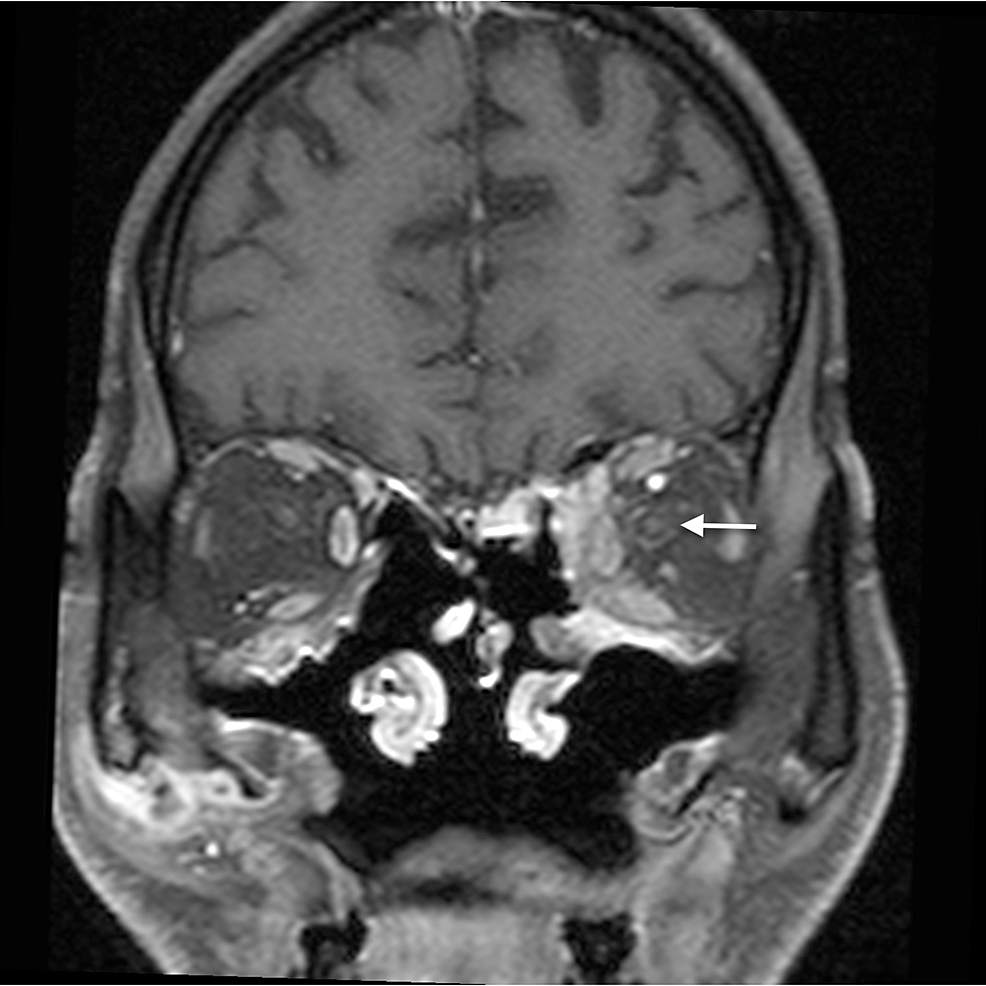

The main complications of orbital cellulitis (Figures 2-4) encountered in our study were:

1. An orbital abscess (Figures 5-6);

2. Preseptal cellulitis and abscess (Figures 7-8);

3. Periorbital cellulitis (Figures 9-10);

4. Dacryoadenitis (Figures 11-12);

5. Optic neuritis/perineuritis (Figure 13);

6. Cavernous sinus thrombophlebitis and thrombosis (Figure 14).

The most common complication of orbital cellulitis was orbital/periorbital abscess formation (eight cases, 53.3%), followed by optic neuritis (four cases, 26.67%), intracranial involvement (four cases, 26.67%), dacryoadenitis (three cases, 20%) and cavernous sinus thrombophlebitis (three cases, 20%).